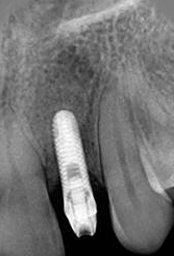

X-ray of Implant

Single Tooth Implant

X-ray of Implant + Abutment

X-ray of Implant +

Abutment + Prosthesis

Placement of Bone Grafting

Abutment+ Prosthesis